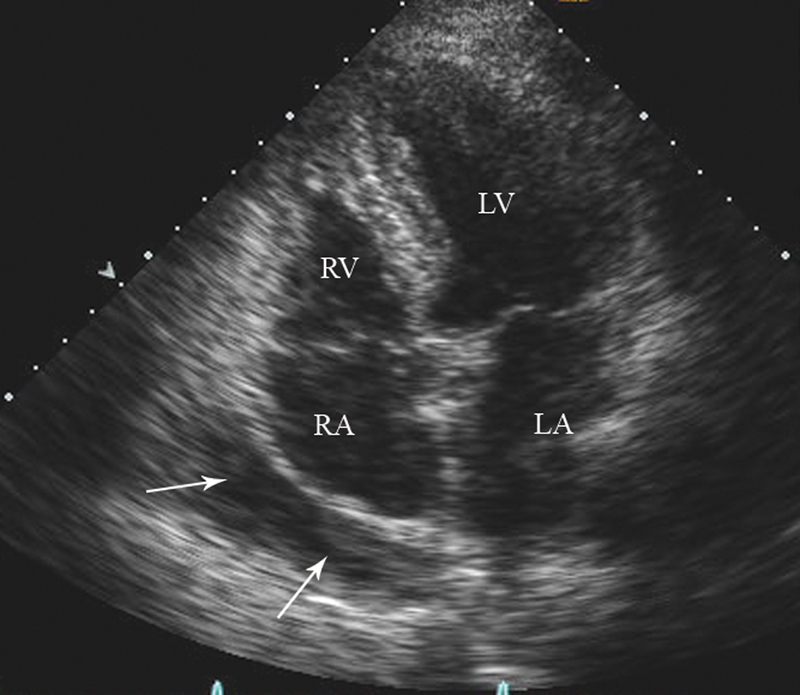

فحوصات تشخيصية لبعض امراض القلب والشرايين التاجية